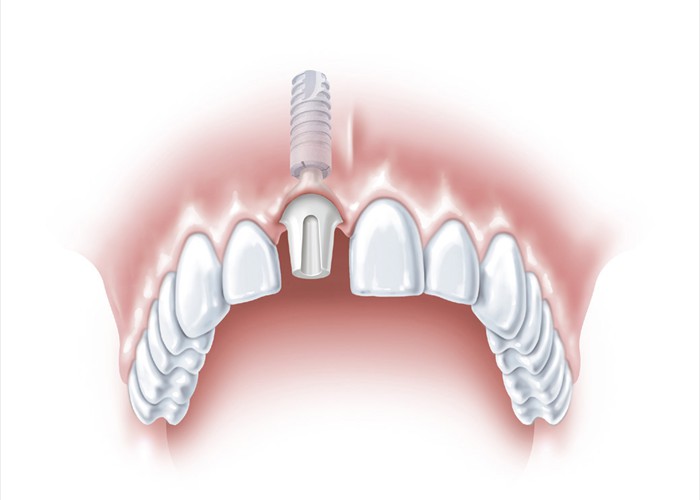

Die beste und zahnschonendste Lösung ist ein Implantat.

Die beste und zahnschonendste Lösung ist ein Implantat.

Hier wird eine Keramikkrone auf das Implantat gesetzt, eine ästhetisch optimale Lösung, bei der die Nachbarzähne nicht beschädigt werden.

Hier wird eine Keramikkrone auf das Implantat gesetzt, eine ästhetisch optimale Lösung, bei der die Nachbarzähne nicht beschädigt werden.